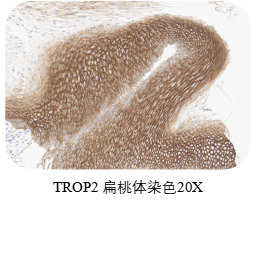

❶ 质控选择

在正常和肿瘤组织中,TROP2染色主要定位于细胞膜,部分伴有较弱的细胞质染色。扁桃体可同时作阴阳性对照,作为阳性对照,扁桃体隐窝上皮表现出较强的膜染色;作为阴性对照,除隐窝上皮外的其他区域应为阴性。选取皮肤作为阳性对照,皮肤的表皮细胞应表现出较强的膜染色。

ACRO IHC实验室目前已建立了成熟的TROP2染色方法与判读体系,适用三阴性乳腺癌、前列腺癌、胰腺癌、卵巢癌、皮肤癌等多个癌种,可快速用于相关肿瘤的临床试验入组筛选与样本检测,部分结果展示如图所示。